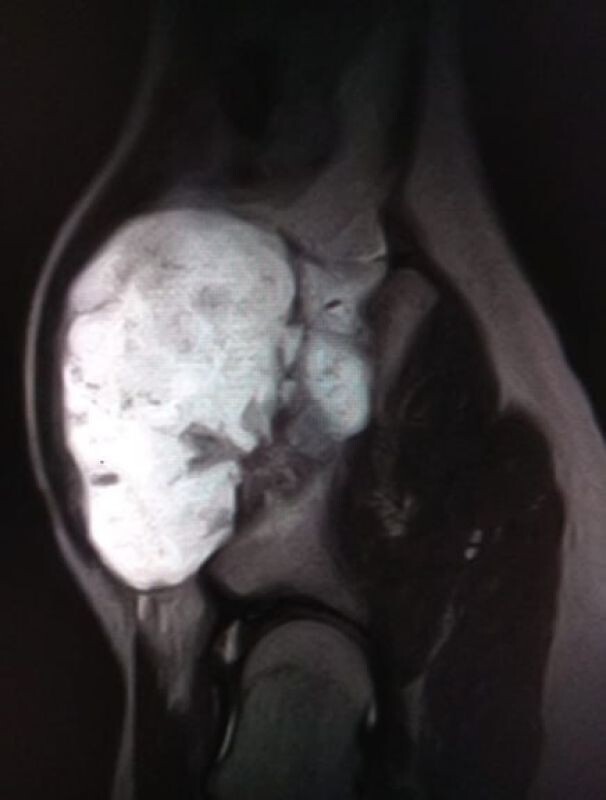

Нарост на кости пациента достиг больших размеров

Подросток наблюдался с редким диагнозом — «экзостозная хондродисплазия». Это заболевание, при котором на кости образуется костно-хрящевое разрастание. У пациента оно достигло внушительных размеров, вызывало боль и причиняло дискомфорт. Также была угроза здоровью тазобедренного сустава.

У пациента нарост появился на тазовой кости, в сложной анатомической области. От хирургов требовалась особенная точность. Бригада врачей бережно удалила нарост, не задев сосуды и зоны роста. Недуг, который беспокоил мальчика, полностью ликвидировали.